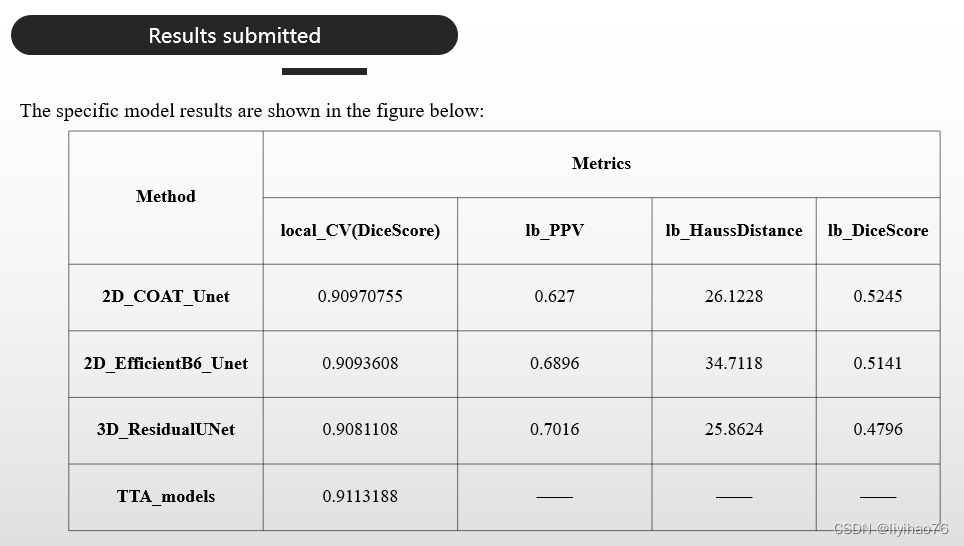

(6) Results submitted

验证集上表现